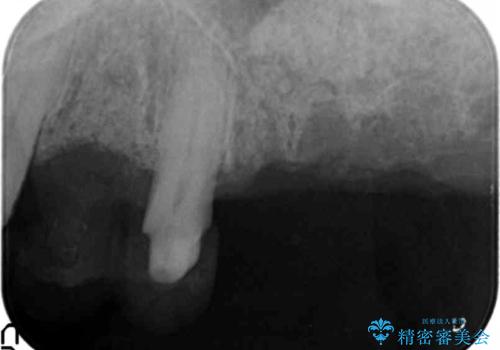

精密検査の結果、重度の歯周病が認められ大きな骨の吸収を認めました。

予後の悪く保存の難しい歯を抜去し、骨の造成を含んだインプラント治療を計画します。